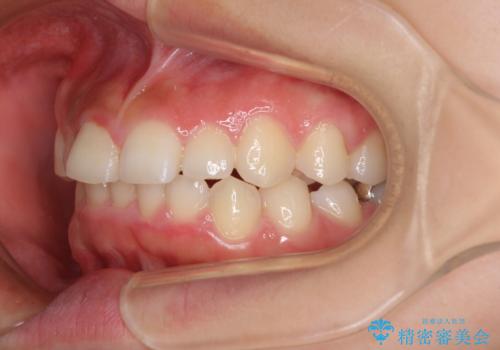

前歯のデコボコと突出感 インビザラインによる矯正治療

- 上下前歯のデコボコと、上顎前歯の突出感を気にして来院された患者様です。

インビザラインによる上下歯列の側方拡大と後方移動、IPR(歯と歯の間を削る)にるスペースの獲得により歯列を整えることとしました。

毎日22時間以上しっかりとマウスピースを装着していただいたので、スムーズに治療が進みました。歯と歯の間を削ることでうまくスペースコントロールでき、1年強で終えることができました。